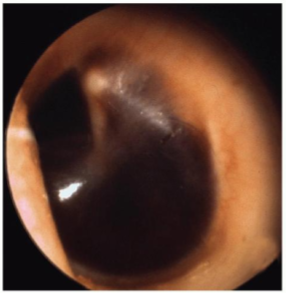

Hemotympanum

Longitudinal fracture

CHL, ossicular separation, TM perf, hemotympanum, bloodyotorrhea